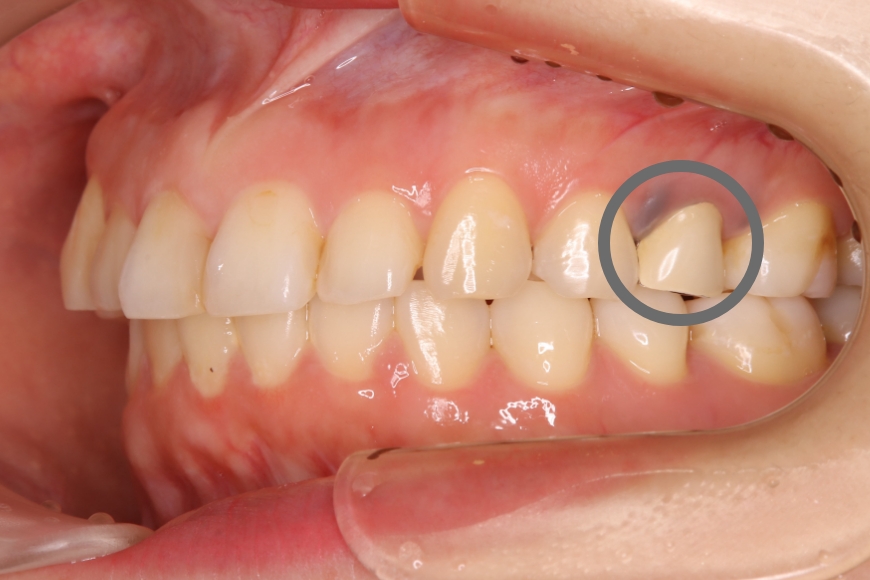

20代女性 上の奥歯へのジルコニア治療およびメタルタトゥーの除去

治療前①

治療内容 奥歯の被せものをやり直したい、また、歯ぐきが黒くて気になるとのことで来院されました。

金属の被せの表面にプラスチックが張り付けてあり、また、使用している金属が溶け出し、歯ぐきが黒くなっていました(メタルタトゥー)。

装着してある全ての金属を除去後、歯ぐきのメタルタトゥーにレーザー照射を行い、健康なピンク色の歯ぐきを回復しました。その後、審美的および耐久性に優れるジルコニアの被せものを装着しました。

治療後は金属アレルギーのリスクがゼロとなり、メタルタトゥーが起こる心配もありません。